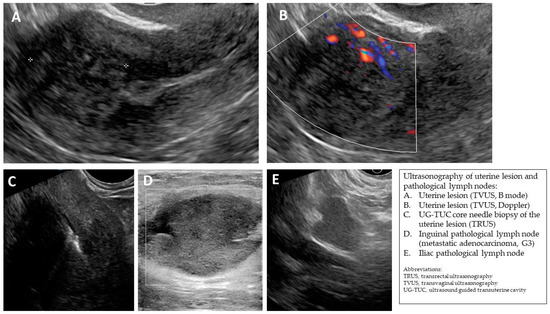

| Case Number (Age, Years Old) | Ultrasound Diagnosis of Uterine Lesion | Figure | Initial Treatment/ Histological Diagnosis Required (Doctor’s Decision) | Initial Patient’s Willingness to Undergo Surgery for the Uterine Lesion | Histology from Core Needle Biopsy | Patient Decision to Undergo Surgery for the Uterine Lesion | Histology from Definitive Surgery | Did Core Needle Biopsy Provided Additional Information to Ultrasound | Did Core Needle Biopsy Provided Useful Information for the Clinical Management |

|---|---|---|---|---|---|---|---|---|---|

| 1 (44) | Typical uterine lesion (myoma) | Figure A1 | No | Yes | Leiomyoma, cellular variant (UG-TUC core needle biopsy) | Yes (lesion enlarged during follow-up) | Leiomyoma, cellular variant | No | Yes |

| 2 (36) | Sarcoma suspicion | Figure A2 | Yes | Tumorectomy, uterus preservation (young age) | LMS (UG-TUC core needle biopsy) | Yes | LMS | No | Yes |

| 3 (37) | Atypical uterine lesion | Figure A3 | Yes | No | Lipoleiomyoma (UG-TUC core needle biopsy) | No | - | Yes | Yes |

| 4 (56) | Atypical uterine lesion | Figure A4 | Yes | Yes | Leiomyoma (transvaginal ultrasound guided core needle biopsy) | Yes | Leiomyoma and adenomyosis | Yes | No |

| 5 (50) | Atypical uterine lesion (metastatic adenocarcinoma G3 in inguinal lymph node) | Figure A5 | Yes | No | Leiomyoma (UG-TUC core needle biopsy) | No | Uterus / tumor not resected because primary urological carcinoma was diagnosed | Yes | Yes |